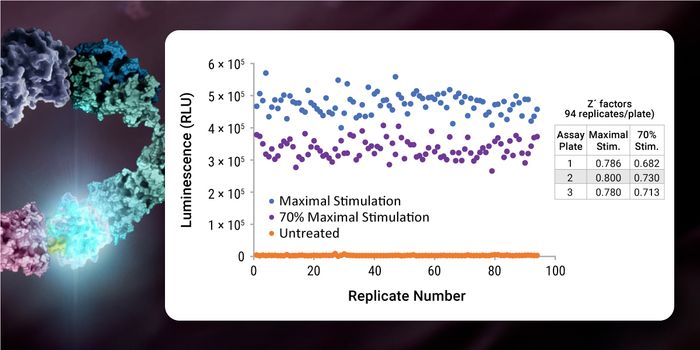

JAN 25, 2024Drug Discovery & DevelopmentDeveloping new pharmaceuticals is a complex and costly process that requires innovation and efficiency. High-throughput ...